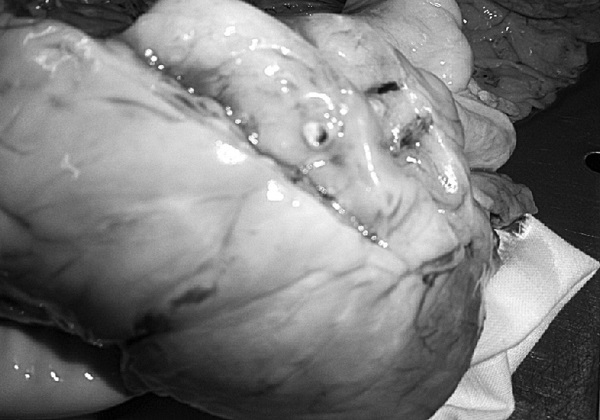

На секции был установлен следующий диагноз.

Основной:

1. Последствия инфаркта головного мозга. Внутренняя гидроцефалия. Атеросклероз артерий виллизиева круга.

2. ИБС. Постинфарктный кардиосклероз. Атеросклероз коронарных артерий.

Фоновый:

1. Артериальная гипертензия.

2. Гипертрофия левого желудочка сердца.

Осложнения:

1. Длительная иммобилизация.

2. Хроническая сердечная недостаточность.

3. Невроангиосклероз.

4. Пролежни.

5. Интоксикация.

6. Отек головного мозга.

Сопутствующий:

Доброкачественная гиперплазия предстательной железы

Последствия ОНМК: постинфарктные кисты головного мозга

Постинфарктный кардиосклероз

Атеросклероз сосудов головного мозга. Отек головного мозга

Атеросклероз коронарных артерий

Гипертрофия левого желудочка

Мускатная печень

Полнокровные легкие

Рис. 1. Результаты аутопсии больного 68 лет